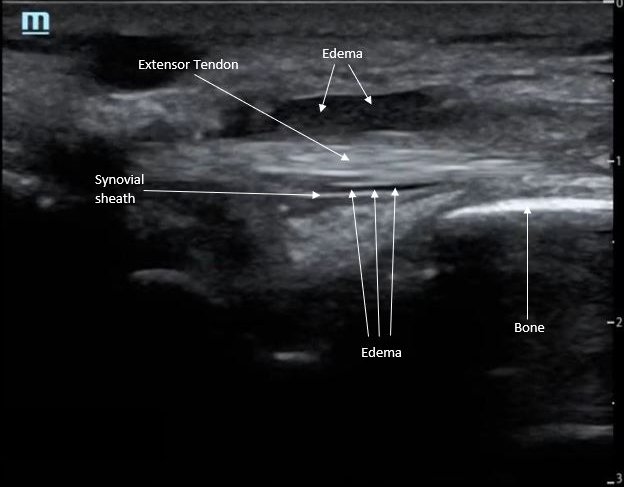

Point-of-care ultrasound of the dorsal aspect of the left hand reveals a heterogenous hypoechoic fluid collection surrounding the extensor tendons (axial view) within the retinaculum consistent with edema. Longitudinal view shows anechoic fluid within the tenosynovium which is located between the anisotropic extensor tendon and linear hyperechoic synovial sheath. Longitudinal view also shows some cobblestoning, or tissue edema, superficial to the anisotropic extensor tendon. The patient’s contralateral right dorsal hand was scanned in a longitudinal view and shows no cobblestoning or hypoechoic fluid under the synovial sheath. The patient was diagnosed with tenosynovitis, and started on intravenous antibiotics.

There is a paucity of literature on extensor tenosynovitis compared with flexor tenosynovitis. The diagnosis of tenosynovitis of the wrist is often clinical using Kanavel’s cardinal signs developed in 1912, though this was developed for flexor, and not extensor tenosynovitis.1 More recently, ultrasound has been used to diagnose tenosynovitis with a sensitivity of 94% and has been shown to be more sensitive than clinical exam.4,5,6 Ultrasound findings may include hypoechoic to anechoic fluid and cobblestoning of the soft tissues, a thickened tendon sheath, and abnormal hypoechoic material within the synovial sheath.5 These ultrasound findings are best seen using a high frequency linear probe oriented in the transverse and longitudinal planes over the dorsal aspect of the hand.6 Our patient’s ultrasound demonstrated cobblestoning of the soft tissues and abnormal hypoechoic material within the synovial sheath; however, we did not measure synovial sheath thickness. While superficial cobblestoning is commonly seen in cellulitis, a thickened synovial sheath and/or abnormal hypoechoic material within the synovial sheath should prompt consideration of tenosynovitis.